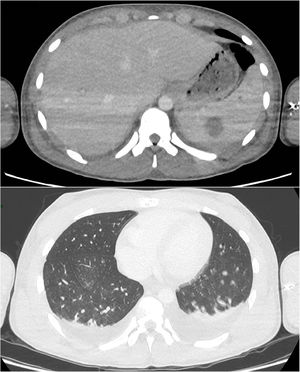

At Day 9, rhabdomyolysis and renal failure improved, so the patient was transferred to the pediatric unit. CT scan performed at Day 10 (Fig. 1) showed extensive lymph node formation in the thorax, with a bilateral pleural effusion. The kidneys, liver and spleen were hypertrophied with multiple hypodense nodular lesions. There are also multiple adenomegalia of the coeliac region and an intraperitoneal effusion.